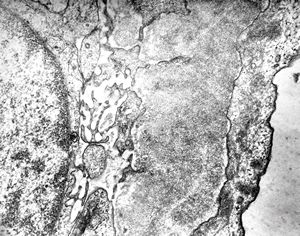

M,22y. | type II membranoproliferative glomerulonephritis